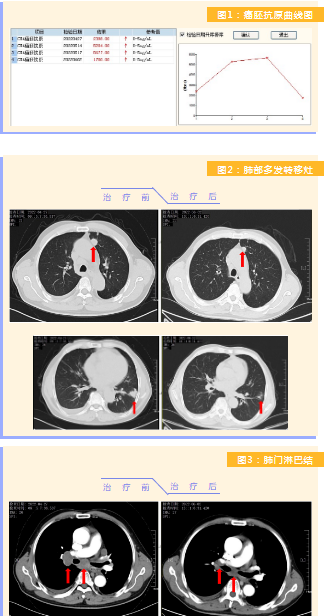

患者完成1周期治療后,上腹部疼痛癥狀基本消失,梗阻性黃疸癥狀緩解,腫瘤指標(biāo)下降(圖1),肺部多發(fā)轉(zhuǎn)移灶消失和縮?。▓D2),雙肺門(mén)淋巴結(jié)縮小(圖3),肝臟多發(fā)轉(zhuǎn)移灶縮小(圖4)。